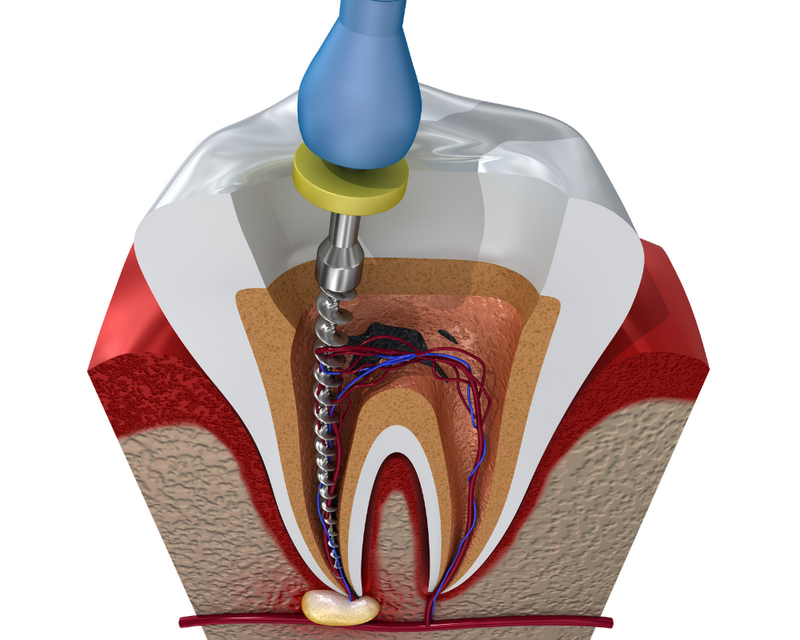

Root Canal Treatment

Root Canal Treatment is a procedure performed on the infected tooth to remove the decay affecting the pulp (underlying tissue containing blood vessels and nerve supply to a tooth). Simple filling procedure cannot restore a tooth’s dental health when the infection has encroached the pulp. Root canal therapy is the only alternative to save such tooth from being extracted. The main objective of root canal treatment is to preserve the infected existing natural tooth by disinfection. During a root canal therapy, access to the root canal present inside the root of a tooth is gained and the infected tissue is removed entirely. Hence Root Canal treatment bypasses extraction of the infected tooth and its replacement procedures thereby saving time and money.